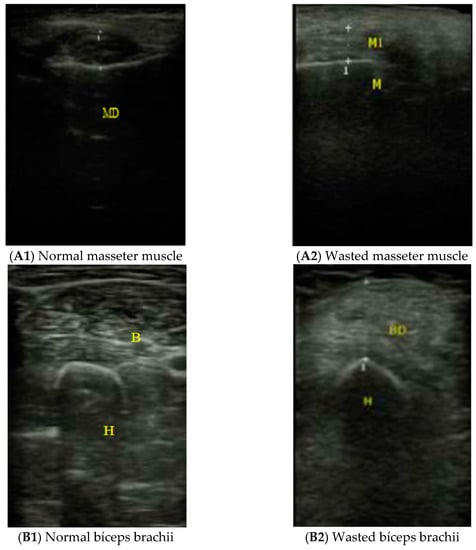

2.2.4. Muscle Ultrasound Exploration